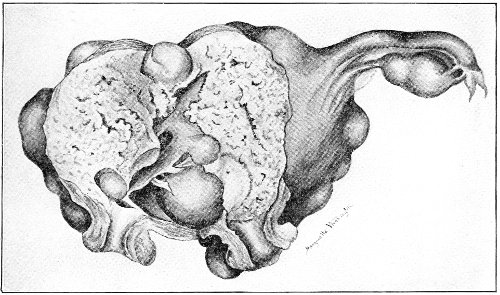

Cysts of the gland may be unilocular if formed at the expense of a single lobule of the gland, or multilocular if several lobules enter into their formation. These cysts may attain the size of the fetal head (Fig. 18).

Cysts of the gland or of the duct are formed by retention of the cyst-contents. The retention is due to occlusion of the duct, usually the result of inflammation. In some cases the duct remains pervious, and the retention is due to the altered character of the secretion of the gland, which becomes too viscous to pass, except under unusual pressure, along the duct.

These cysts contain clear yellow or chocolate-colored 42 fluid. The diagnosis of cyst of the vulvo-vaginal gland is usually not difficult. If we are in doubt in regard to the fluid character of the tumor, this may be determined with the exploring-needle.

Inguinal hernia, hydrocele of the canal of Nuck, cysts of the round ligament, and sacculated cysts of old hernial sacs may be mistaken for cysts of the vulvo-vaginal glands. In such cases, however, the tumor lies more in the upper and outer part of the labium majus, and extends to, and may be connected with, the external inguinal ring.

Cysts of the vulvo-vaginal glands should be treated by free incision and packing, or by extirpation. If the sac is emptied by the aspirator or by a small incision, it will refill. The best method is to extirpate the cyst. In case there has been no inflammatory action binding the cyst to surrounding structures, extirpation without rupture is easy. If rupture occurs, the cyst-wall may be dissected off with the knife or removed with the curved scissors. The wound may be immediately closed with deep and superficial sutures.